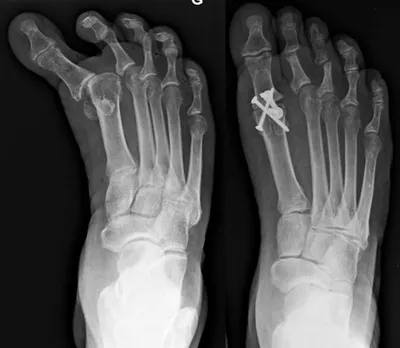

Hallux Varus Pre and Postop with 1st MPJ Fusion Below

Hallux Varus Postop and Preop with 1st MPJ Fusion Below

Deviation of the great toe off of the 1st metatarsal in long standing deformity with history of previous surgery as proof by the surgical screw at the base of the 1st metatarsal. The great toe joint (1st MPJ) is severly degenerated from arthritis (left). Surgical correction of this condition involves fusion of the joint with a cross screw technique (right) which will eliminate pain and difficult with walking and other activities.